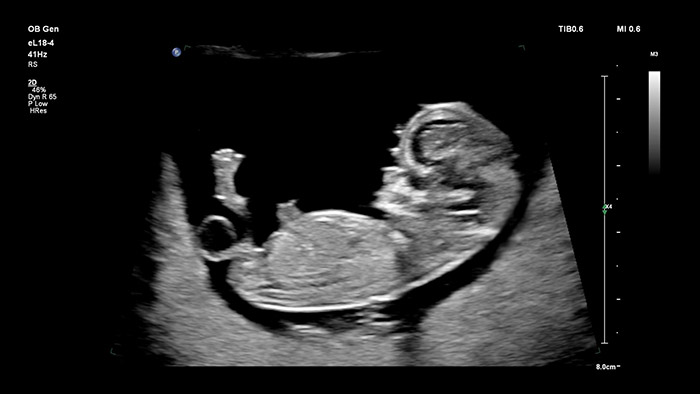

El transductor eL18 -4 de Philips con MicroFlow Imaging salva todos los obstáculos gracias a la adquisición de imágenes 2D de alta resolución y a la detección ultrasensible del flujo sanguíneo; estos elementos están pensados para evaluar el estado de salud general del feto en las primeras etapas del embarazo, momento en el que una resolución excelente y un diagnóstico fiable resultan determinantes. El transductor V9-2, muy versátil y está específicamente diseñado para obstetricia; emplea la potencia de la tecnología PureWave Crystal para ofrecer unas imágenes 2D y 3D óptimas; no obstante, también es ligero en comparación con otros de su categoría.